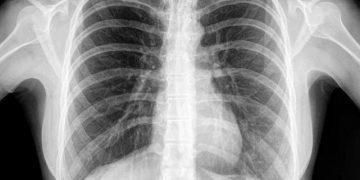

Jakarta, SatukanIndonesia.com – Menjaga kesehatan paru-paru sangat penting di tengah merebaknya pandemi Covid-19. Banyak yang ingin memiliki kehidupan yang lebih sehat. Namun, sayangnya masih banyak dari mereka yang tak sadar akan kesehatan paru-paru.

Hal tersebut dibuktikan dengan masih tingginya angka penyakit yang menyerang paru-paru. Di Indonesia, misalnya, kanker paru-paru menjadi kanker pembunuh nomor satu, utamanya pada pria dewasa.

Padahal, sama seperti jantung dan bagian tubuh lainnya, paru-paru akan menua seiring waktu berjalan. Paru-paru menjadi kurang fleksibel dan kehilangan kekuatannya, yang bisa membuat seseorang jadi sulit bernapas.